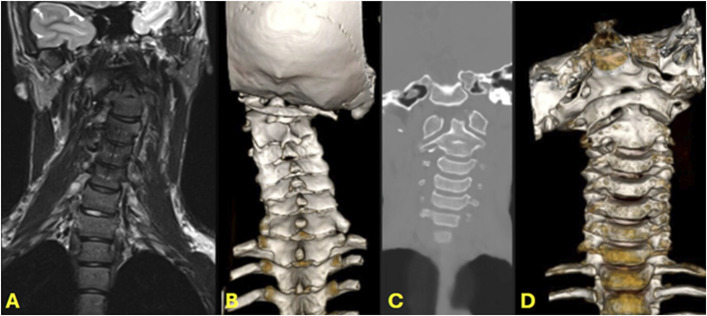

背景:计算机断层扫描(CT)和磁共振成像是常用的影像学研究,用于评估儿童脊柱患者。在尸体研究中,与传统CT (tCT)相比,新型mri生成的合成CT (sCT)图像在准确性上几乎相等。这一最新进展使得在没有有害电离辐射的情况下,骨骼和软组织解剖的可视化成为可能。迄今为止,没有文献报道使用sCT评估儿童脊柱病变。本研究旨在评估sCT在治疗患有各种脊柱疾病的儿童和青少年患者中的临床应用。方法:回顾性分析某第四护理医院2023年10月至2024年9月的小儿脊柱患者。纳入标准包括任何接受sCT脊柱评估的患者。收集患者人口统计学和影像学结果。对于任何在sCT后3个月内接受传统CT (tCT)的患者(n = 10),比较冠状、矢状和轴向序列的骨解剖学测量(每次扫描共10次测量)。还比较了sCT和tCT的官方放射学读数。结果:25例患者行脊柱sCT(2例颈椎,23例腰椎)。适应症包括排除先天性肌性斜颈(2例)、峡部裂(13例)、峡部滑脱(2例)、脊柱侧凸/背痛(4例)、慢性背痛(4例)、腰骶过渡性疼痛(4例)。共进行了176次脊柱骨解剖测量。将tCT与sCT进行比较,62.5%的测量值差异小于0.5 mm, 95.5%的测量值差异小于1 mm, 4.5%的测量值差异大于或等于1 mm。结论:sCT是评估儿童骨性脊柱的一种无辐射的替代成像方式。sCT提供儿童骨骼解剖的三维成像,与tCT相比,大部分在1毫米内。我们相信sCT在儿童和青少年人群中具有重要的临床应用价值,可以在不将患者暴露于辐射和使用单一成像研究的情况下诊断骨骼和软组织病变。证据等级:三级。有关证据水平的完整描述,请参见作者说明。

Results: Twenty-five patients underwent sCT of the spine (2 cervical and 23 lumbar). Indications included rule out congenital cervical anomalies in congenital muscular torticollis (2 patients), spondylolysis (13), spondylolisthesis (2), scoliosis/back pain (4), chronic back pain (4), and back pain with transitional lumbosacral anatomy (4). A total of 176 measurements of spinal osseous anatomy were performed. Comparing tCT with sCT, 62.5% of the measurements differed by less than 0.5 mm, 95.5% by less than 1 mm, and 4.5% differed by 1 mm or more.

Conclusion: sCT is a radiation-free alternative imaging modality for the evaluation of the osseous spine in children. sCT provides 3-dimensional imaging of the child's bony anatomy, largely within 1 mm compared with a tCT. We believe sCT has significant clinical utility in the pediatric and adolescent population, allowing the diagnosis of both bony and soft tissue pathologies without exposing patients to radiation and using a single imaging study.